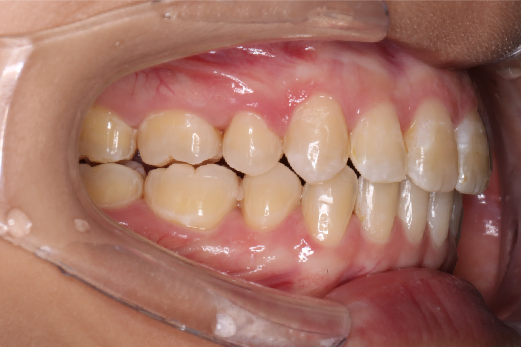

• 磨牙,尖牙I类关系,中线齐

IntraoralExamination(2016-08.31,Wu)

2018.11.14  术后磨牙尖牙I类关系,中线齐,覆合,覆盖正常